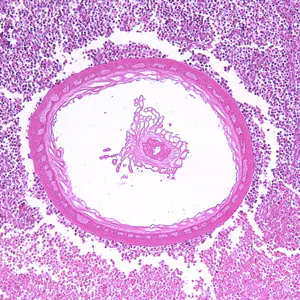

Acanthocephalans in tissue, stained with hematoxylin and eosin (H&E).